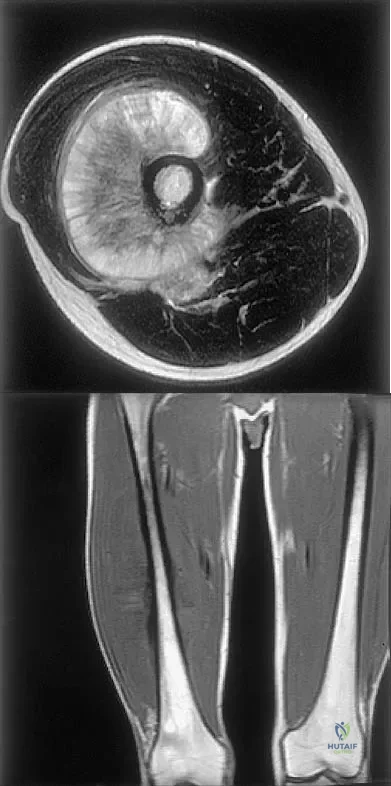

Figures 35a and 35b show the axial T2-weighted and coronal T1-weighted MRI scans of a patient who has enlargement of the right thigh. What is the most likely diagnosis?

Explanation